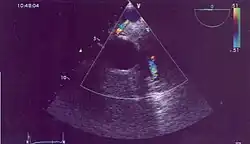

| Possible communication between left coronary artery and pulmonary artery in a 45-year-old woman with Bland-White-Garland syndrome. | |

Historically ALCAPA was diagnosed with conventional angiography. Today echocardiography is easily used. It can provide direct visualisation of the anomalous coronary artery and other associated structural abnormalities, and it can also assess myocardial function. The use of pulse and color-flow doppler can sometimes visualise reversal flow in the pulmonic artery. Other non-invasive methods used are computed tomography (CT) as well as magnetic resonance imaging (MRI), which enable a direct visualisation of the arteries as well as the myocardial viability.[3]